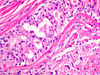

CASO N° 3 (Dr. Abel e Dr. Delgado)

Paciente do gênero masculino, 21 anos de idade, apresenta uma lesão no palato duro.